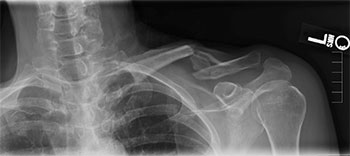

Photo Courtesy of Aaron Mark Chamberlain, MD, MSc, MBA, FAAOS